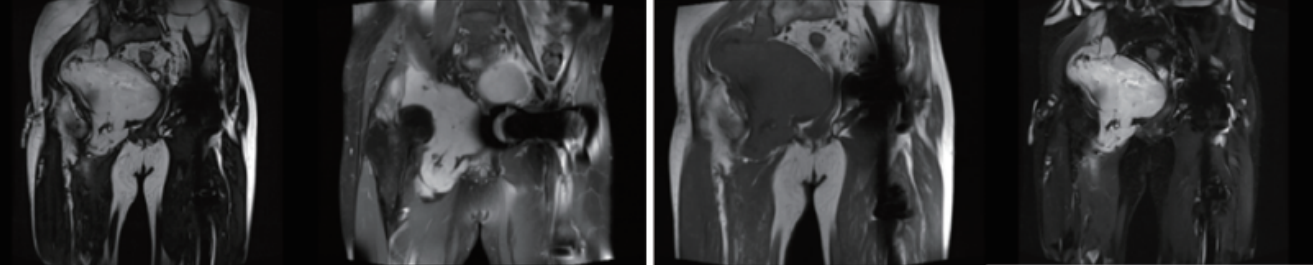

案例圖

骨與軟組織腫瘤